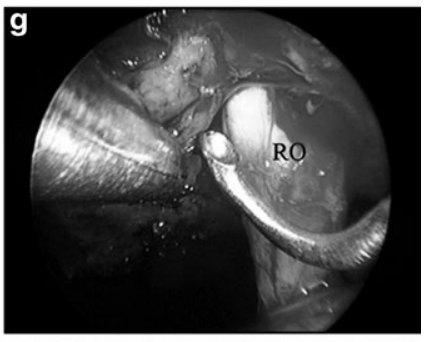

g 于右视神经(RO)内侧继续切除肿瘤。